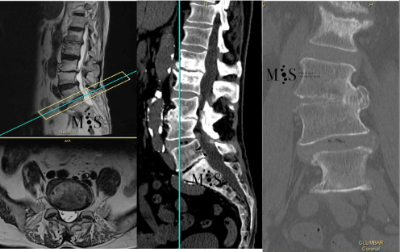

Scoliosis is a deformity/curving of the spine in the frontal plane. It can be congenital (present since birth) or degenerative (developed during the aging process). Progressive degeneration of the intervertebral disks (because of age, weight, activity, etc.) can lead to the spine to deform and curve in, ending up as a degenerative scoliosis, also called "de novo" because it is of "new" appearance in comparison to congenital scoliosis which has been present since birth.

Scoliosis lead to a curved back with the patient having problems walking with a straight back, and it can lead to an intense back pain. The spinal deformity and curving can lead to an impingement of the nerve roots which can cause radiating leg pain.

In these painful cases, surgery is indicated to (partially) correct the deformity and mainly to reduce/eliminate the pain generated by the scoliosis. In the most severe scoliosis cases an osteotomy (chiseling of a vertebral bone) may be required to straighten up the spine and reduce its deformity.